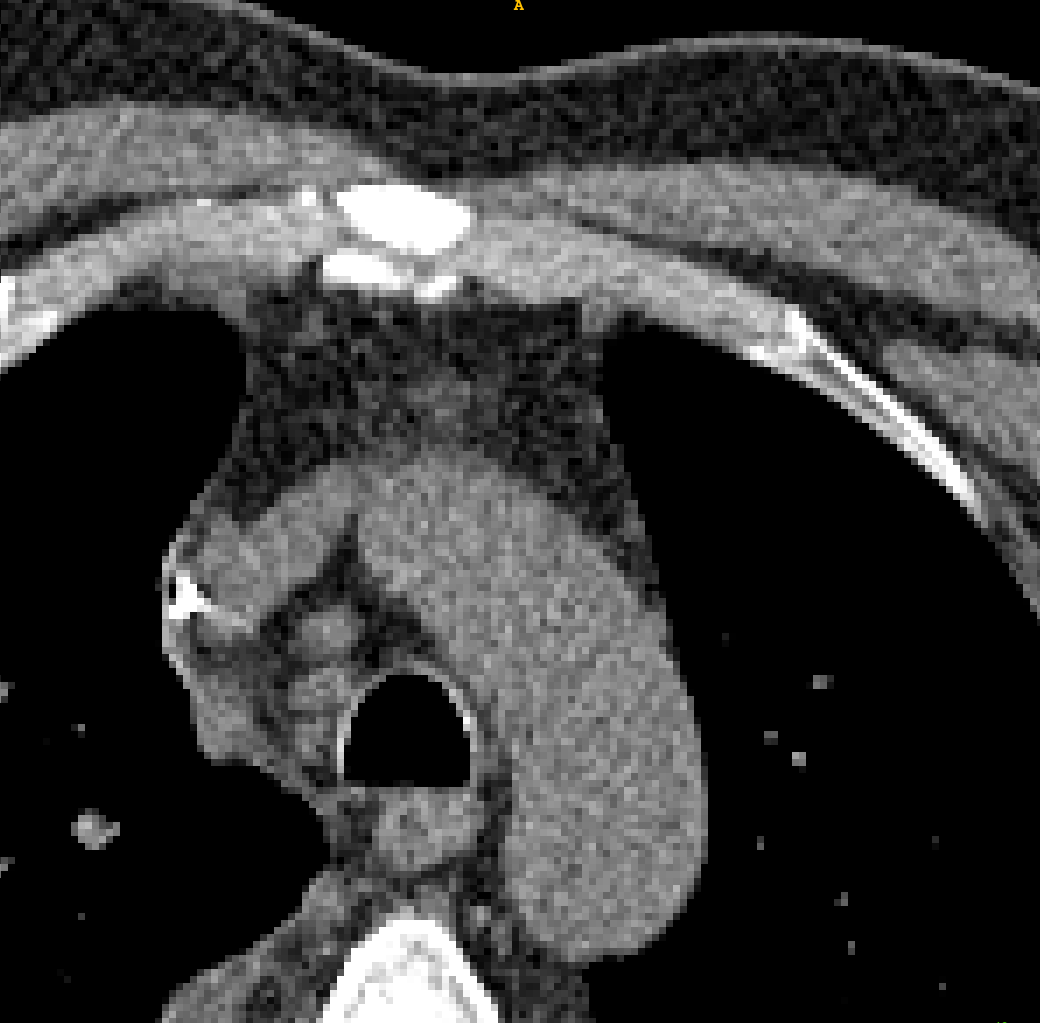

TABLE V: Visualization result on SegTHOR. Gray image registration result(row 1-2) shows the fitting ability of various methods. Mask image registration result(row 3-4) shows the regional continuity of various methods. The mask includes four parts: heart(green), aorta(yellow), trachea(blue) and esophagus(red).

[Uncaptioned image] [Uncaptioned image] [Uncaptioned image] [Uncaptioned image] [Uncaptioned image] [Uncaptioned image]

F M VoxelMorph Ants deedsBCV Ours

We selected four images of large deformations occurring at different locations from different CT, the visualization results are shown in Table V.

Rows 1-2 shows the CT gray image registration results. The task is to register MM to FF. From the visualization of gray image results, we can see that although ANTs and deedsBCV has high dice scores, the visualization results look unrealistic. Meanwhile, deep learning methods look smoother. The sixth column shows the results of our method. The fitting effect is improved compared to previous methods.

Rows 3-4 shows the mask registration results. The background of each image is FF. We could judge the performance by observing the fitting degree of the mask and background. In many practical tasks, we use a registration algorithm to register MM’mask to get the mask of FF. There may be a situation where the gray image fitting is good, but the mask result is poor. This may be because the continuity of the registration field is not good enough.